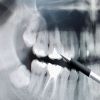

الحشوة اللاصقة حل وقائي لتسوس أسنان الأطفال

تُعرف الحشوات الواقية اللاصقة بأنها حشوات مصنوعة من مادة خاصة بيضاء أو شفافة يتم استخدامها على الأسطح الماضغة للأسنان الخلفية دون الحاجة لتحضير... المزيد

السكري وصحة الفم والأسنان

يتسبب ارتفاع نسبة السكر في الدم بطرحه بشكل تلقائي عن طريق البول مما يؤدي إلى زيادة تكرار التبول وبالتالي فقدان السوائل يتسبب بالعطش والجفاف في... المزيد